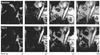

Figure 5

Treatment monitoring with fluorodeoxyglucose (FDG) PET and CT in a patient with locally advanced distal esophageal cancer (arrows). In each image set, the image on the left is a longitudinal section from the neck to the pelvis and the image on the right is a cross-section through the plane containing the tumor. The tumor demonstrates intense FDG uptake before therapy (day 0). FDG uptake decreases markedly on day 14 of the first chemotherapy cycle. Quantitatively, FDG uptake by the tumor decreased from a standard uptake value of 9.2 to 4.2. After completion of preoperative chemotherapy, the tumor was resected. Histopathology demonstrated less than 10% of viable tumor cells in the resected specimen. Permission obtained from the American Society of Clinical Oncology © Weber WA (2006) Positron emission tomography as an imaging biomarker. J Clin Oncol 24: 3282–3292.